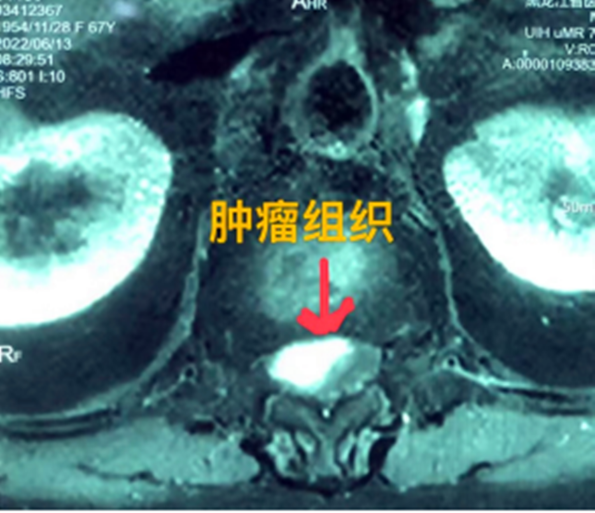

據(jù)省醫(yī)院神經(jīng)外一科陶宇醫(yī)生介紹,家住外地的張大娘最近總感覺雙下肢疼痛、無力,且排尿困難及便秘,伴有行走困難。時(shí)間長了,張大娘病情逐漸加重,劇烈的疼痛甚至讓她無法完整入睡。在當(dāng)?shù)蒯t(yī)院,張大娘按腰椎肩盤突出接受治療,但未見好轉(zhuǎn),隨后進(jìn)行的胸椎MRI(核磁共振)檢查,結(jié)果不禁讓張大娘和家屬瞠目結(jié)舌,原來張大娘患的竟然是少見的脊髓腫瘤。

張大娘住進(jìn)了黑龍江省醫(yī)院神經(jīng)外一科,該科孫國章主任醫(yī)師熱情地接待了張大娘,并邀請(qǐng)骨外一科專家共同為她進(jìn)行了聯(lián)合會(huì)診。發(fā)現(xiàn)張大娘病情十分復(fù)雜棘手,脊髓腫瘤體積較大,充滿髓腔且神經(jīng)已經(jīng)完全受壓,需要手術(shù)來完整切除。同時(shí)還發(fā)現(xiàn)張大娘的胸腰部曾受過兩次外傷,伴有多處骨折,這對(duì)接下來的手術(shù)操作帶來一定影響。